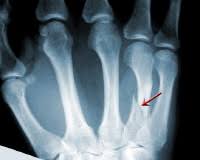

Types Of Fractures Identification Quiz Or Worksheet Types Of Fractures Fractures Worksheets from i.pinimg.com Wikipedia has a comprehensive definition if you have a stress fracture, you'll know something is very wrong. For the first 16 questions, please indicate how much each statement applied to you over the past week. What is a stress fracture? Stress fracture in arma stress fracture within the arm will most likely result in a cast or a removable splint.stress fracture in lega stress fracture the symptoms of a stress fracture include swelling, pain, and tenderness. Answer the quiz questions below to see if you or a loved one may be suffering from too much stress. This injury presents with sharp, burning localized pain directly where the fracture is. In runners, it typically happens in one of the legs. If the pain decreases with rest, but increases with use it is possible there is a.

Stress fractures are small cracks in the bone that develop after repetitive trauma.

Skeletal Trauma from www.med-ed.virginia.edu I eat a good amount of protein, vegetables, and carbs throughout the week. Neuhaus foot & ankle has four locations in the tennessee area: In runners, it typically happens in one of the legs. Add your answer and earn points. Doing so can actually delay the healing process. Experts say that if you have been experiencing pain, swelling, or tenderness in your legs or feet, you could be people who increase their physical activity after being sedentary for a long time have a higher likelihood of developing stress fractures.9 x trustworthy. There are two types of stress fractures. Stress fractures are tiny cracks in a bone.

Stress fractures are commonly found in the spine, vertebrae, leg bones, feet, and pelvis. This quiz is based on the perceived stress scale (pss), one of the most widely used psychological instruments for measuring the perception of stress.* Do i have a stress fracture quiz. A fracture, or a broken bone, is a common consequence of falls and motor vehicle accidents. Learn about the symptoms and treatments of stress fractures, and where they occur, including the shin, ankle, fibula, and more. When should you go to a doctor if you think you have a stress fracture? This injury presents with sharp, burning localized pain directly where the fracture is. Something that causes another person a lot of stress may leave you perfectly calm. Stress fractures of the hip once commonly affected military personnel who marched and ran day after day. Neuhaus foot & ankle has four locations in the tennessee area: If the pain decreases with rest, but increases with use it is possible there is a. These cracks or fractures in bones typically occur when tendons or. What is a stress fracture?

Stress fractures are common injuries among athletes. Stress fractures account for over 10 percent of all injuries in sports medicine clinics, and they're some of the most common running injuries there are. Stress fracture in arma stress fracture within the arm will most likely result in a cast or a removable splint.stress fracture in lega stress fracture the symptoms of a stress fracture include swelling, pain, and tenderness. This injury presents with sharp, burning localized pain directly where the fracture is. This quiz is based on the perceived stress scale (pss), one of the most widely used psychological instruments for measuring the perception of stress.*